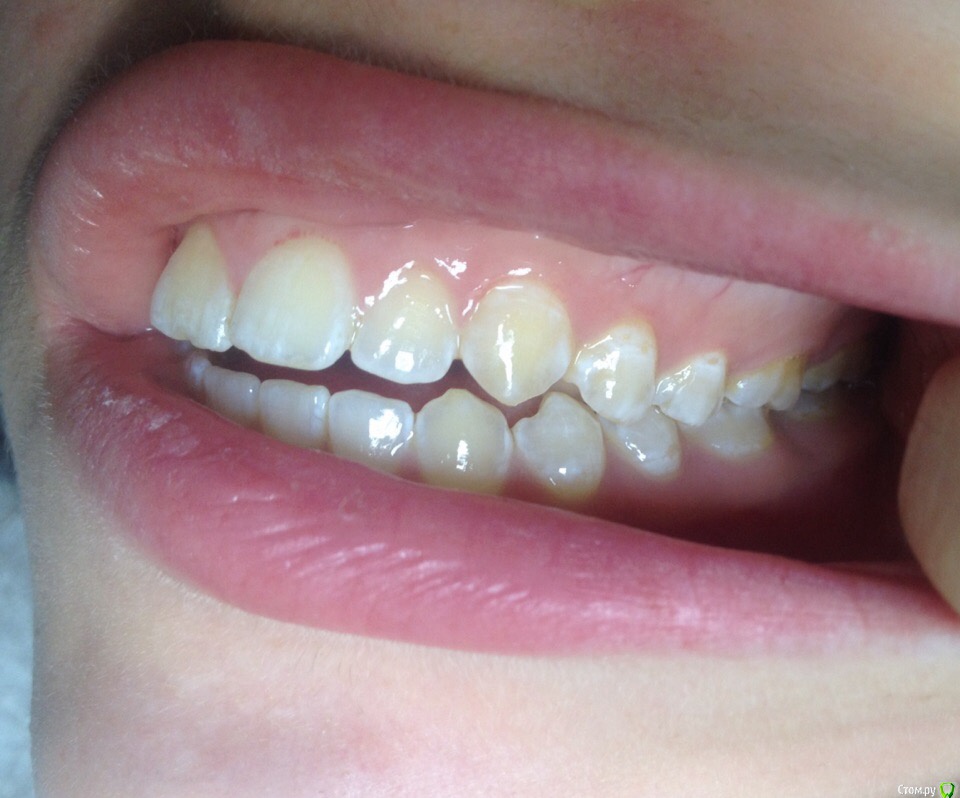

КошкинДом Опубликовано 3 сентября, 2019 Поделиться Опубликовано 3 сентября, 2019 Приветствую всех!Меня зовут Александра, мне 25 лет и я ипохондрик, переживаю в данный момент из-за своих зубов. Возможно кто-то из вас сможет дать мне совет Пол года назад у меня немного заболел левый ВНЧС, было неудобно спасть, затем все прошло и больше ничего не беспокоит до сих пор, только иногда хрустит в левом суставе и легкий дискомфорт в ухе после еды. Я заметила что в течении этих 6 месяцев мой прикус открылся ~2мм Вот мое фото 2017:А вот сейчас: Также прикрепляю два фото, ТРГ и ОПТГ: Мой вопрос: Меня сейчас ничего не беспокоит в моих зубах, можно ли и дальше спокойно жить? Если кто-то сталкивался с подобным дайте совет Всем хорошего дня 1 Ссылка на комментарий

krokomot Опубликовано 4 сентября, 2019 Поделиться Опубликовано 4 сентября, 2019 Открытый прикус требует лечения. Ссылка на комментарий